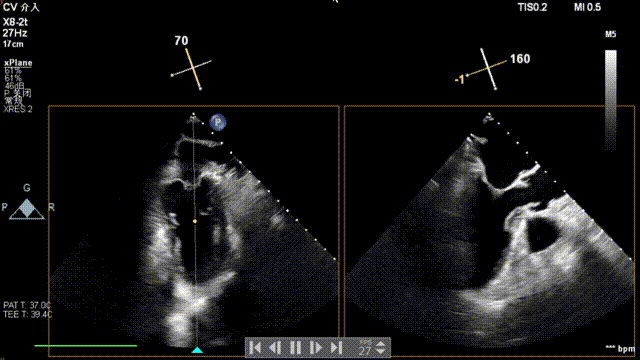

全麻后,二尖瓣夹合器系统在心前区的肋间切开3-4CM小切口,暴露心脏的心尖位置,送系统送入左心房,顺利到达病变二尖瓣区域。在经食道超声辅助下,术者通过反复评估二尖瓣反流位置、抓捕位置、反流程度,首先在2偏3区位置处于二尖瓣闭合线垂直进行巧妙夹合。在2区靠近3区位置处植入了1枚ValveClamp®MVC-IIf夹,最终评估评估反流降至轻度,平均跨瓣压差降至2mmHg,手术取得圆满成功。

术中超声(关键步骤)